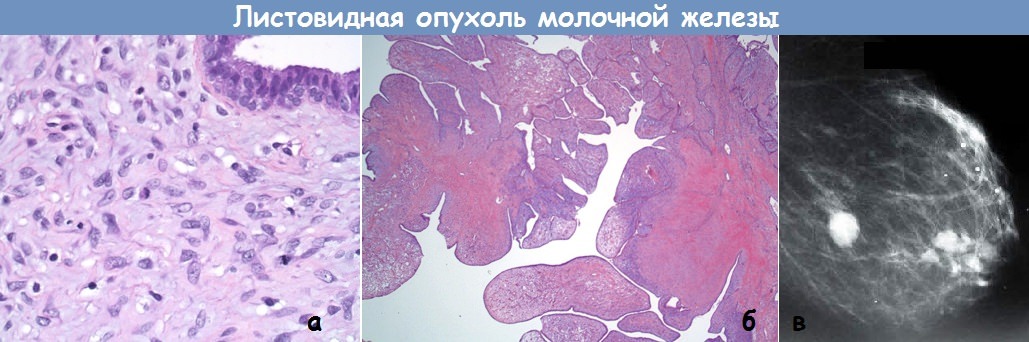

Исследование: микропрепарат молочной железы в медицине

Раздел: Снимки-откровения